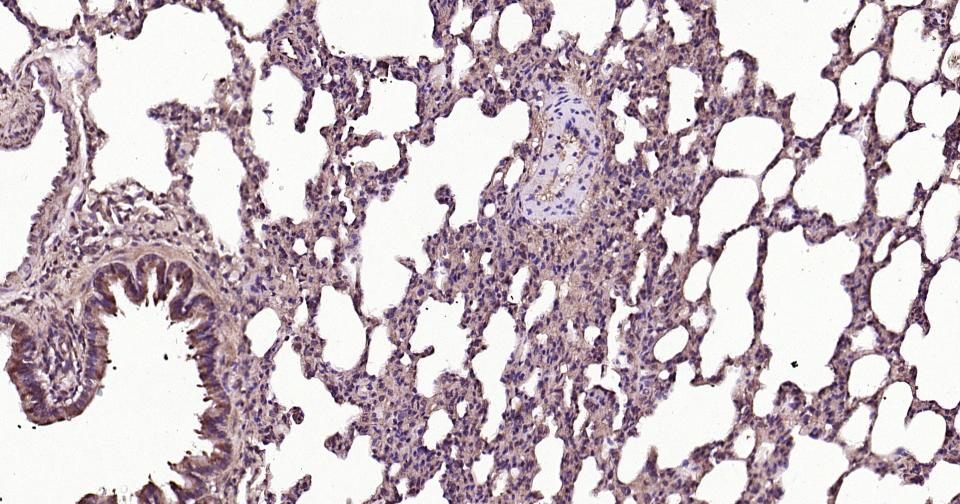

| IHC-P | Human, Mouse, Rat | 1:100-500 | |

| IHC-F | Human, Mouse, Rat | 1:100-500 | |

| IF | Human, Mouse, Rat | 1:100-500 | |

| ELISA | Human, Mouse, Rat | 1:5000-10000 |

交叉反应: Human, Mouse, Rat